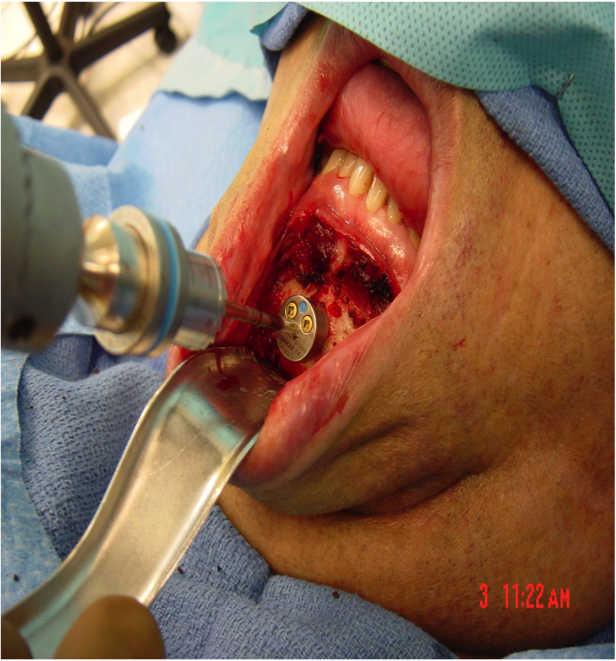

This procedure places tension on the tongue, limiting the posterior from shifting during sleep. The procedure starts with a small incision made inside the lower lip. Then, the surgeon moves away all the soft tissue to expose the lower jaw. Small rectangular cuts are then made in the lower jaw directly in front of the lower front teeth. This area attached to the genioglossus muscle is then moved forward and turned slightly. To hold this bone fragment in place, the surgeon puts in a titanium screw to immobilize it.

The photos on this website are from real surgeries performed by Dr. Ulloa. Due to the

graphic nature of the images and content, viewer discretion is advised.